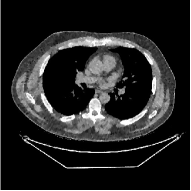

This section compares the reconstruction quality and runtime among the proposed MBIR method, PWLS-ST-, and other three MBIR methods, PWLS-EP, PWLS-DL, and PWLS-ST-. Table I shows that, for both 2D and 3D sparse-view CT reconstructions of the XCAT phantom, the proposed PWLS-ST- model outperforms PWLS-EP and PWLS-ST- in terms of RMSE. In addition, PWLS-ST- using a square transform (of size ) achieves lower RMSE than PWLS-DL using an overcomplete dictionary (of size ) for 2D sparse-view reconstructions. Fig. 3(a) and Fig. 4 show the reconstructed images for 2D and 3D phantom experiments, with different reconstruction models and different number of views. (See the corresponding error maps in the supplement.) The proposed PWLS-ST- consistently gives more accurate image reconstructions compared to other MBIR methods. Specifically, PWLS-ST- has smaller errors in the heart region (see zoom-ins in Fig. 3(a)) of 2D reconstructions than PWLS-DL and PWLS-ST-. In addition, compared to PWLS-ST-, PWLS-DL and PWLS-ST- have some ringing artifacts around the edges with high transition, e.g., edges between air and soft tissues. (See a comparison of profiles of PWLS-ST- and PWLS-ST- in the supplement.) In particular, PWLS-ST- and PWLS-DL give more visible ringing artifacts for 2D reconstruction from fewer views, and PWLS-ST- has these ringing artifacts for 3D reconstructions regardless of the number of views (see zoom-ins in Fig. 4). Table II reports runtimes of different MBIR methods in reconstructing the -views XCAT phantom scan. (FBPConvNet is a non-MBIR method and its runtime for processing a image is approximately one second with a TITAN Xp GPU.) While providing better reconstruction quality, the proposed Algorithm 1 of PWLS-ST- has shorter runtime compared to the algorithms of PWLS-DL and PWLS-ST- in Section III-A. Similar to the PWLS-EP algorithm, the reconstruction time of the PWLS-DL, PWLS-ST-, and PWLS-ST- algorithms can be further reduced by using ordered subsets [51].

Fig. 3(b) shows that when tested on the clinical scan data, the proposed PWLS-ST- method improves reconstruction quality in terms of noise and artifacts removal (e.g., see zoom-ins for soft-issue regions), and edge preservation (e.g., see zoom-ins for bone regions), compared to PWLS-EP and PWLS-ST-. Compared to PWLS-DL, PWLS-ST- achieves comparable image quality, but requires less computational complexity.

| (a) 2D fan-beam CT experiments |